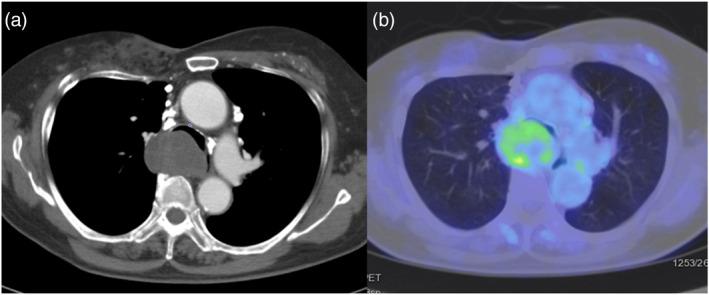

Schwannomas are classified as neurogenic tumors and are the most frequent nerve sheath tumors in the paravertebral mediastinum. Recently, the addition of endobronchial ultrasound-guided intranodal forceps biopsy (EBUS-IFB) using standard-sized biopsy forceps (SBFs) to endobronchial ultrasound-guided transbronchial needle aspiration (EBUS-TBNA) for metastatic lymph nodes in lung cancer patients reportedly improved the quality and quantity of the obtained specimens without significant complications. However, reports on the usefulness of this technique for benign diseases remain scarce. Here we report a case of schwannoma in the middle mediastinum, which was diagnosed by EBUS-IFB using SBFs, despite inadequate specimens obtained via EBUS-TBNA. An 80-year-old woman presented with dyspnea and a 5-cm sized middle mediastinal tumor. EBUS-TBNA and EBUS-IFB using SBFs were performed for histological diagnosis. No complications were associated with the bronchoscopy procedure, and schwannoma was solely diagnosed using the EBUS-IFB specimens. EBUS-IFB using SBFs is potentially useful for diagnosing benign diseases, including schwannomas, which are often difficult to diagnose with EBUS-TBNA.